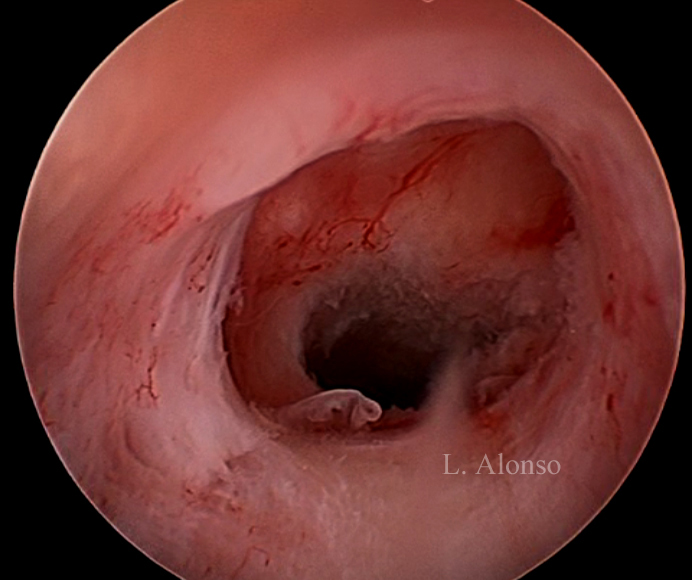

Hysterosonography enhance visualization of the isthmocele even when there is no blood accumulation inside of it. Hysteroscopy is the “Gold Standard” technique for the diagnosis of isthmocele. Hysteroscopy allows direct visualization of the anterior and posterior borders of the isthmocele that some authors define as an anterior and a posterior arch, the isthmocele is actually the area contained between these two arches.